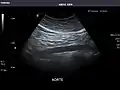

Standard measurement of the abdominal aorta[4]

It can be used on the abdominal aorta to detect or exclude abdominal aortic aneurysm. For this purpose, the standard aortic measurement for abdominal aortic aneurysm is between the outer margins of the aortic wall.[4]

Aorta: Visualized portions normal in caliber, 16 x 15 mm.